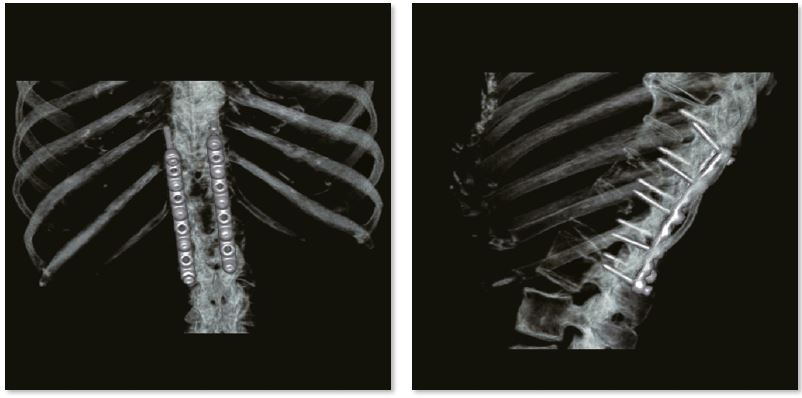

Фіксація поперекового відділу хребта

Для стабілізації заднього відділу хребта та збереження хребетного каналу використовується внутрішня фіксація. Зображення SEMAR забезпечують чудову деталізацію хребетного каналу без артефактів. Міжхребцеві дискові простори звужені та дегенеративні в цій частині поперекового відділу хребта.

3D зображення поперекового відділу хребта

Звичайне зображення

Зображення з SEMAR